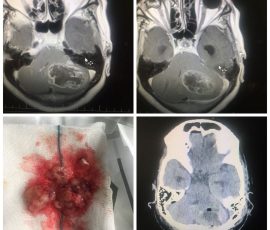

تشخیص تومور مغزی

- تصویربرداری با MRI برای مشاهده دقیق محل و اندازه تومور

- سی تی اسکن جهت بررسی توده، تورم یا خونریزی در مغز

- نمونه برداری از بافت مغز برای تعیین نوع تومور

جراحی

یکی از رایجترین روشهای درمان تومور مغزی، جراحی است که با هدف برداشتن کامل یا حداکثر بخش ممکن از تومور انجام میشود. انتخاب بهترین جراح تومور مغزی میتواند تاثیر زیادی بر بهبود وضعیت بیمار و کاهش علائم داشته باشد. میزان امکان برداشت تومور به محل آن در مغز و نزدیکی به نواحی مهم بستگی دارد، و جراح با دقت فوقالعاده کار میکند تا کمترین آسیب به بافتهای سالم وارد شود. در بسیاری از موارد، جراحی به کاهش فشار بر مغز و بهبود علائم کمک قابل توجهی میکند.